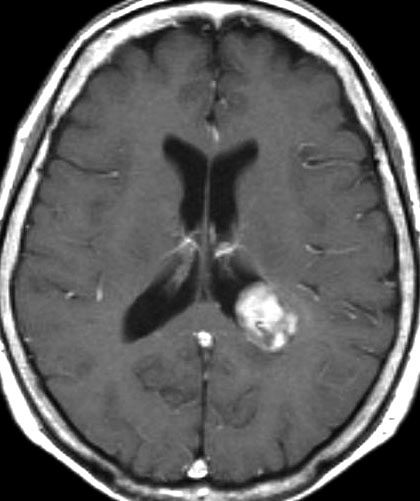

12歳時,私のところへ来た時のガドリニウム増強像です。開頭手術で扁桃体を含めて全摘出してから発作は止まり,術後3年で抗てんかん薬は中断できています。